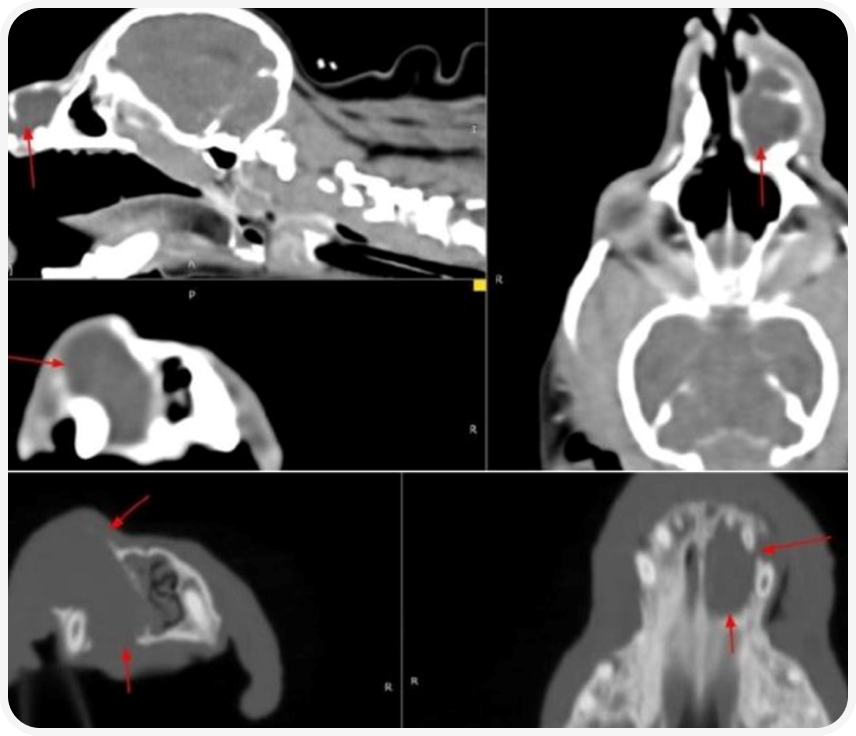

Жалобы: около 6 месяцев назад заметили отек носа слева, появилось храпение, обращались в стороннюю клинику, было назначено КТ-исследование головы, предоперационные исследования – ока, б/х, кгг крови, ЭКГ, ЭХОКГ.

По обследованиям значимых изменений не выявлено. Заключение КТ-исследования головы предоставлено.

Целостность скелета нижней челюсти справа: альвеола 410 зуба умеренно расширена.

Целостность скелета нижней челюсти слева: альвеолы 310 и 309 зубов расширены. Височно-нижнечелюстные суставы: без патологических изменений.

Костная структура турецкого седла: без патологических изменений.

Ретробульбарное пространство: без патологических изменений.

Носовые ходы: полостное образование левой верхнечелюстной области пролабирует в носовую полость (см. описание «Целостность скелета верхней челюсти слева»). Просвет хоан сужен.

Носовая перегородка: в ростральной части не визуализируется.

Решетчатая кость: рисунок решетчатого лабиринта симметричный, проходимость не нарушена.

Область носоглотки: без патологических изменений.

Заключение: Полостное образование левой верхнечелюстной кости с литической деструкцией и инвазией в носовую полость (одонтогенный абсцесс). Комплекс стоматологических патологий. Сужение просветов внутренних отверстий наружных слуховых проходов.